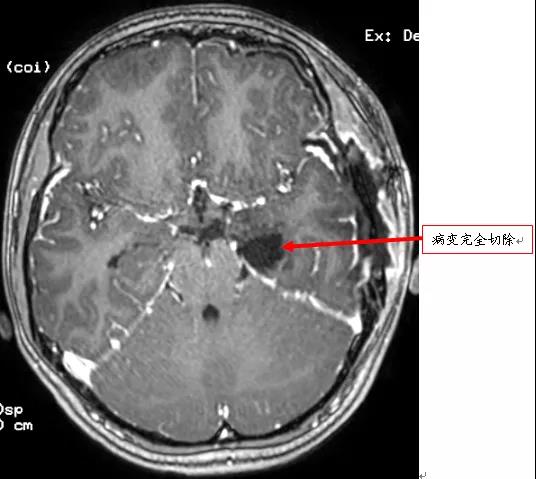

术后MRI显示病变完全切除

术后三天,小李可以下床活动,一周后康复出院。目前,小李已返回学校,随访一个多月,没有再次发生癫痫。